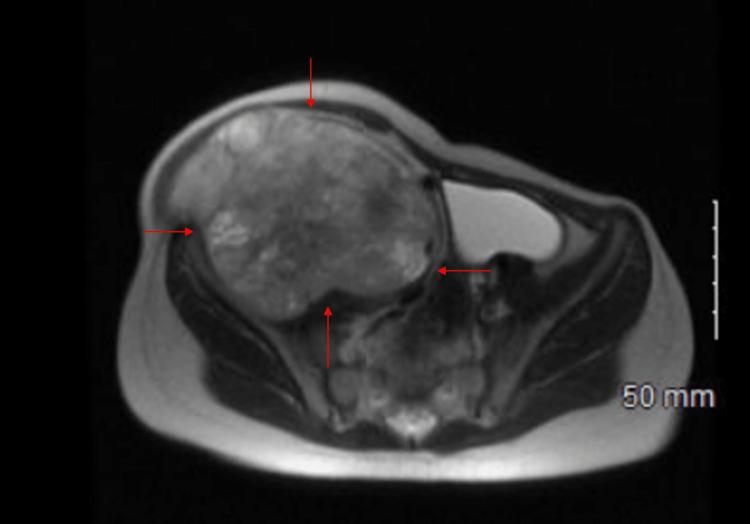

Li-Fraumeni syndrome (LFS) is an autosomal dominant disorder that often results from mutations that impair the functions of the tumor suppressor gene p53. LFS is categorized as a hereditary cancer predisposition syndrome in which patients frequently suffer from an elevated degree of onset and incidence of neoplastic malignancies. Among the different pathogenic variants of LFS, TP53 is one of the most frequently encountered ones. A four-year-old female is reported in this vignette, with a rare c.375+1G>T pathogenic variant in the TP53 gene consistent with an LFS diagnosis. To our knowledge, this is the first reported "germline" example of this variant in the literature. Initially, the patient presented to the emergency department due to concerns of progressive swelling and firmness of a mass in the patient's right abdomen. Further imaging and analysis revealed a rhabdomyosarcoma of the pelvis secondary to LFS. In addition to this, the patient's brother and mother both were positive for the same LFS mutation allowing us to make a definitive LFS diagnosis. Our patient then underwent neoadjuvant chemotherapy, radiotherapy, and eventually a resection of the main neoplastic lesion. Among pediatric LFS patients, the risk of suffering secondary and/or multiple cancers is pathologically elevated. That said, it is crucial to perform genetic analysis tests for pediatric oncology patients, especially those patients with hereditary predisposition to cancers. Considering the poor prognosis of most TP53 mutations, it is of utmost importance to implement prompt and systematic care for patients diagnosed with LFS.

李-弗劳梅尼综合征(LFS)是一种常染色体显性疾病,通常由损害肿瘤抑制基因p53功能的突变引起。LFS被归类为遗传性癌症易感性综合征,患者经常遭受肿瘤恶性肿瘤发病程度和发病率的升高。在LFS的不同致病变体中,TP53是最常遇到的变体之一。本病例报告了一名4岁女性,其TP53基因存在罕见的c.375+1G>T致病变体,符合LFS诊断。据我们所知,这是文献中首次报道的该变体的“种系”实例。最初,患者因担心右腹部肿块逐渐肿胀和变硬而就诊于急诊科。进一步的影像学检查和分析显示,继发于LFS的骨盆横纹肌肉瘤。除此之外,患者的哥哥和母亲均检测出相同的LFS突变呈阳性,这使我们能够做出明确的LFS诊断。我们的患者随后接受了新辅助化疗、放疗,并最终切除了主要肿瘤病灶。在儿童LFS患者中,患继发性和/或多种癌症的风险在病理上有所升高。也就是说,对儿科肿瘤患者,尤其是那些有癌症遗传易感性的患者进行基因分析检测至关重要。考虑到大多数TP53突变的预后较差,对诊断为LFS的患者实施及时、系统的护理至关重要。